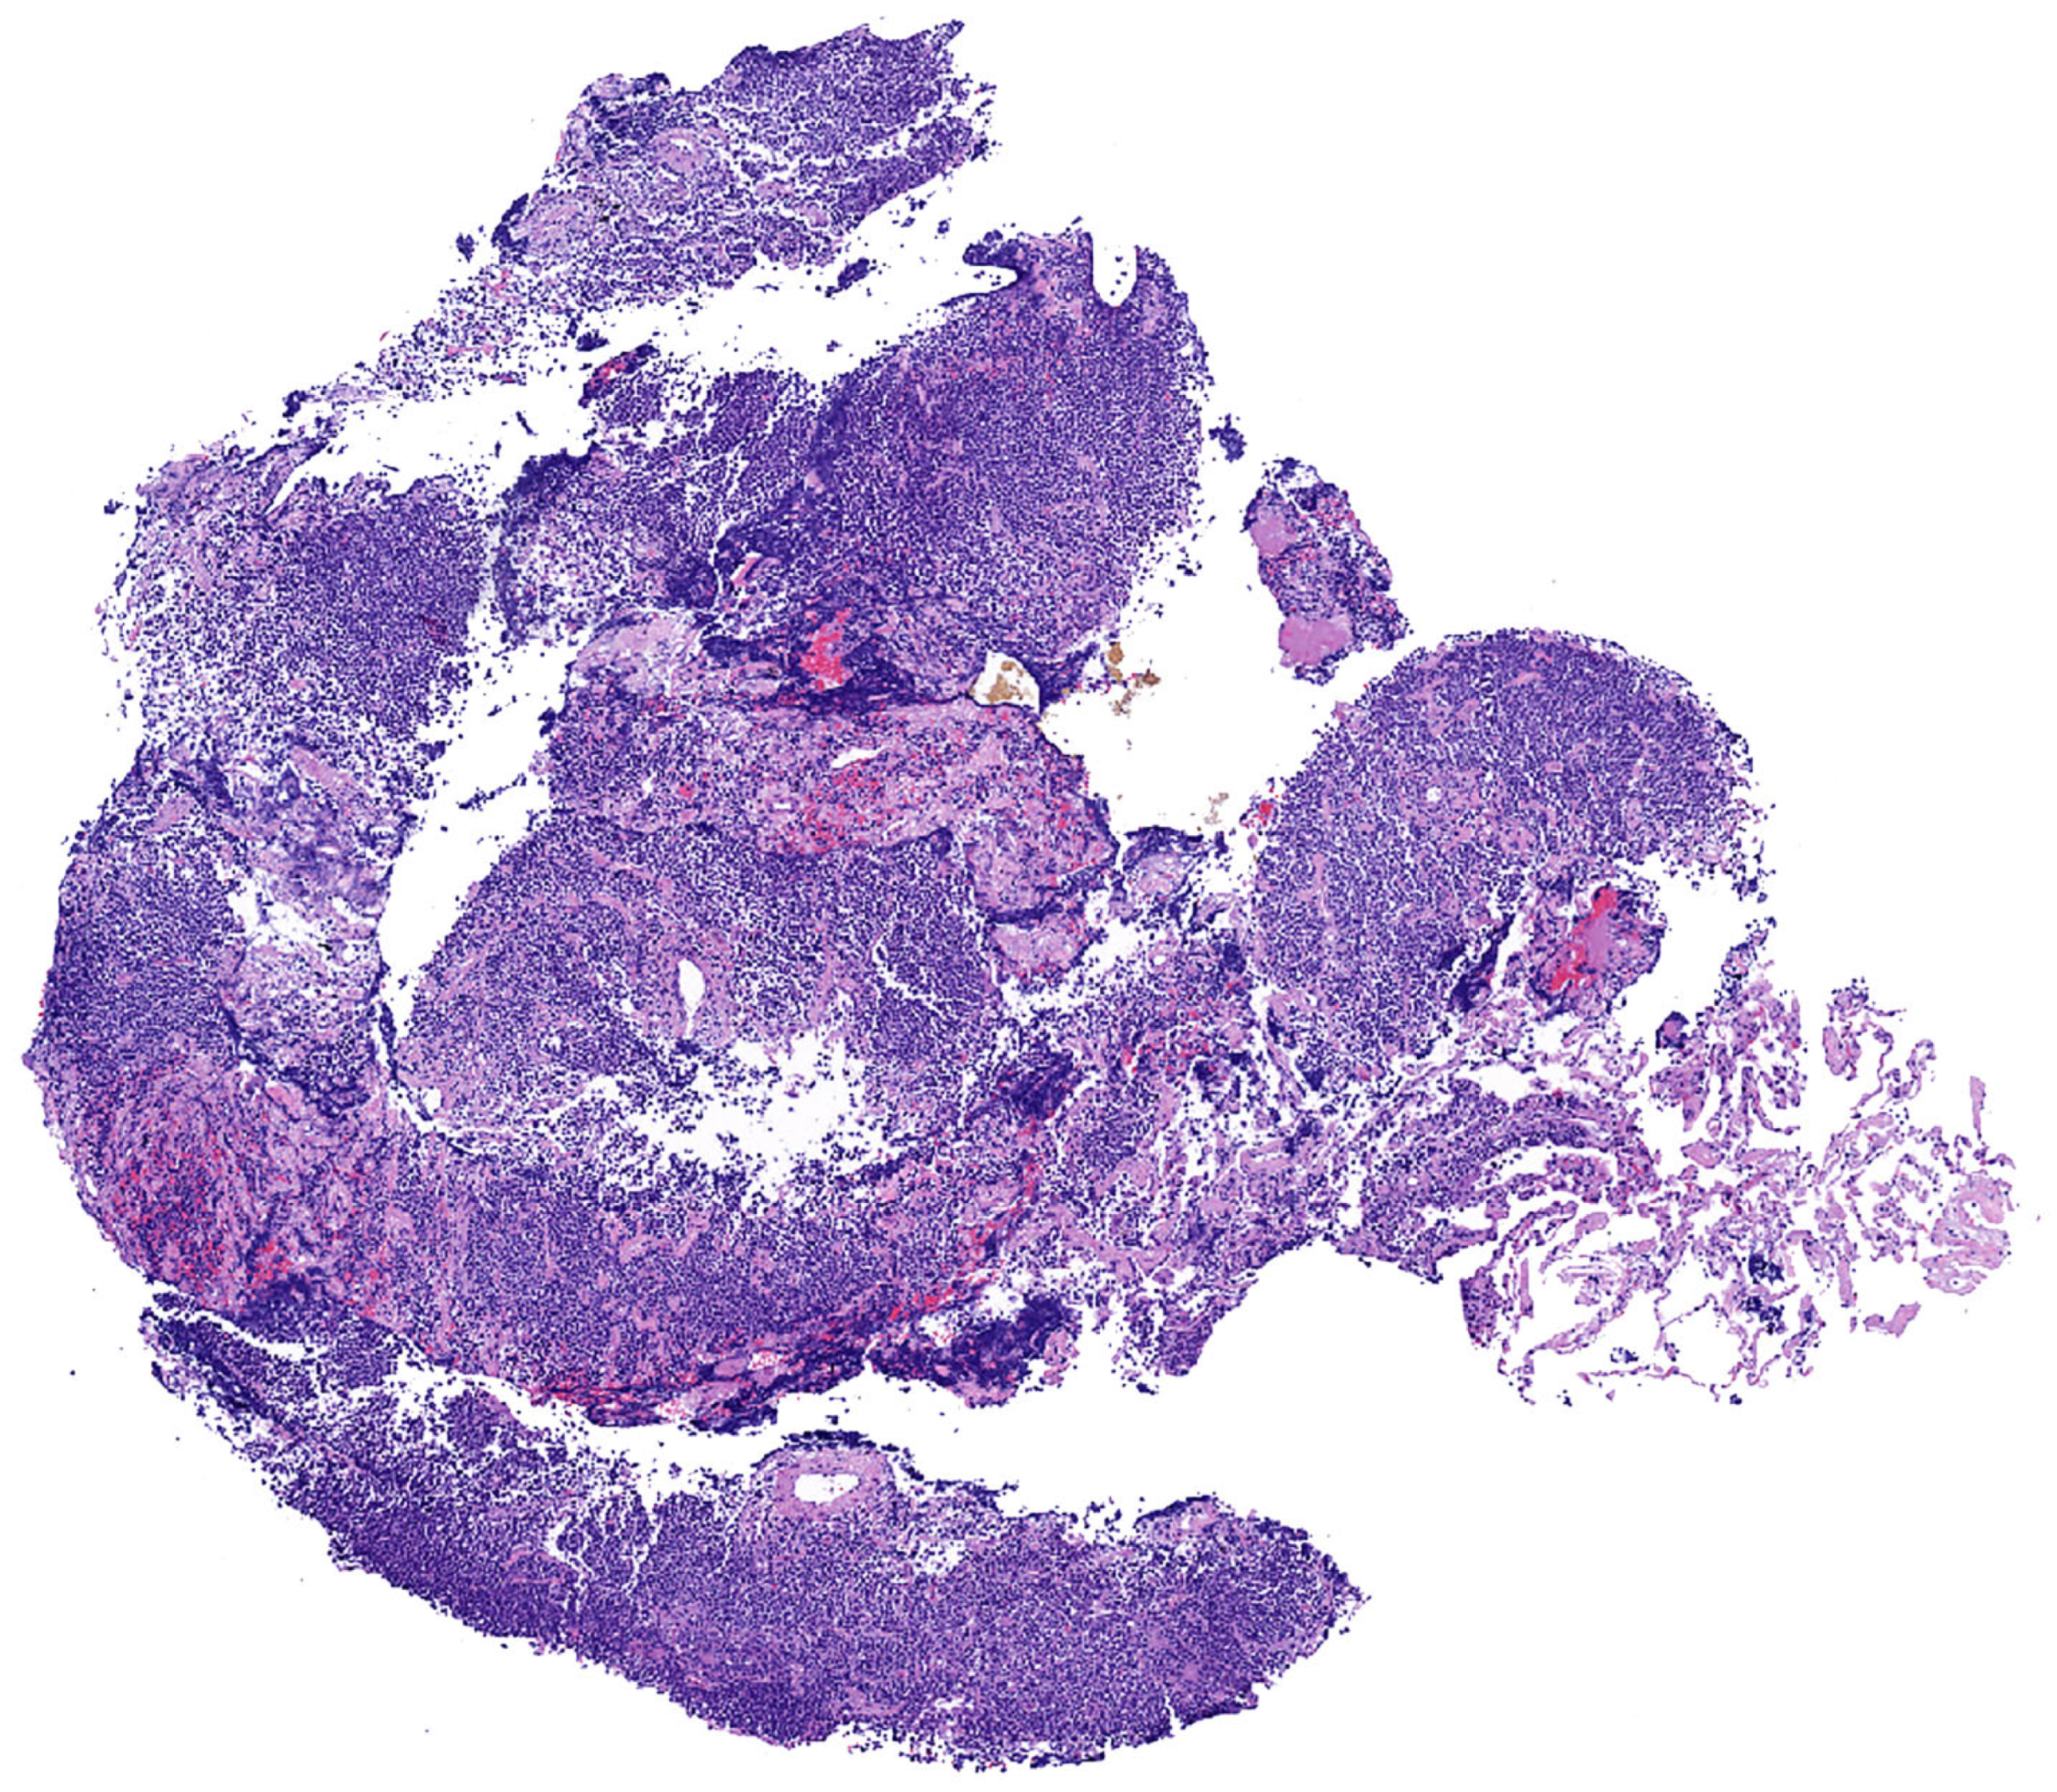

Histopathologic features in biopsies. MALT lymphoma is a polymorphic lymphoma composed predominantly of sheets of small lymphocytes, centrocyte-like cells, and monocytoid cells, with few scattered large immunoblast-like cells and a variable number of plasma cells. This process typically effaces the lung parenchyma (Figure 2 and Figure 3).

Figure 2.

Pulmonary MALT lymphoma; core biopsy. There is effacement of the lung architecture by small cell lymphoma with associated areas of fibrosis.